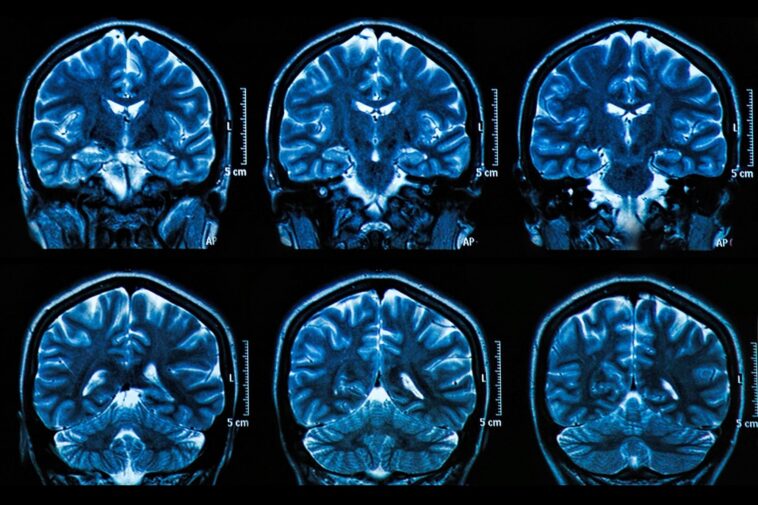

Utiliser l’IRM fonctionnelle (IRMf), les chercheurs ont examiné les schémas d’activité cérébrale des participants lorsqu’ils visionnaient des images appartenant à de larges catégories de scènes et d’objets panoramiques. Certaines images ont été répétées, permettant ainsi de mesurer les schémas d’activité cérébrale provoqués par les catégories d’images, ainsi que par les éléments de stimulus individuels. Les participants comprenaient des groupes d’adultes jeunes et âgés en bonne santé – 24 hommes et femmes âgés en moyenne de 22 ans et 24 hommes et femmes âgés en moyenne de 69 ans.

Sabina Srokova PhD’22 et le Dr Michael Rugg, directeur du Center for Vital Longevity, ont publié une étude dans The Journal of Neuroscience examinant la dédifférenciation neuronale, l’âge et les capacités de mémoire. Crédit : Centre pour la longévité vitale/Université du Texas à Dallas